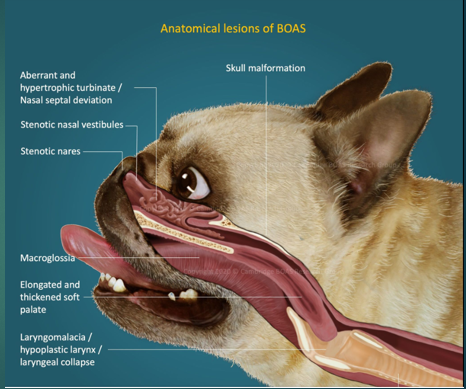

Brachycephalic obstructive airway syndrome in Dogs

Bulldog

Pug

Pekingese

French Bulldog

Boxer

Stenotic nares

Narrowing of the nasal passages, this increases resistance, making breathing in and out more difficult for the paitent

Oversized tongue

Tongue is too big for their moth, can push on soft plate

Elongated soft palate

Effects the epiglottis so can aspirate more easily

Hyperplastic larynx

Overgrowth of soft tissue in the larynx, leading to obstruction

Hypoplastic trachea

Trachea is narrower

Brachycephalic obstructive airway syndrome

The problems we see in these breeds are the consequences of trying to move air with all this increased resistance. To breathe they need to move O2 through the resp tract to the lungs, these issues with the soft tissues that we’ve highlighted cause resistance to air flow, this then increases Resp effort and rate to get more air in, this increases the negative pressure which makes the issue worse – negative pressure caused by them trying to overcome the resistance means that we get more resistance, more swelling of soft tissues and thus more negative pressure. We will often see abdominal effort with BOAS breathing.